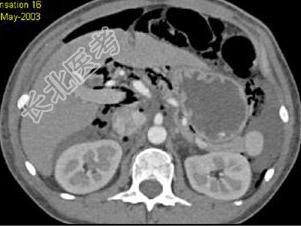

- 单项选择题根据所提供的图像,最可能的诊断是 ( )

A、穿孔后气腹

B、正常结构

C、肝炎

D、胰腺炎

E、以上都不是